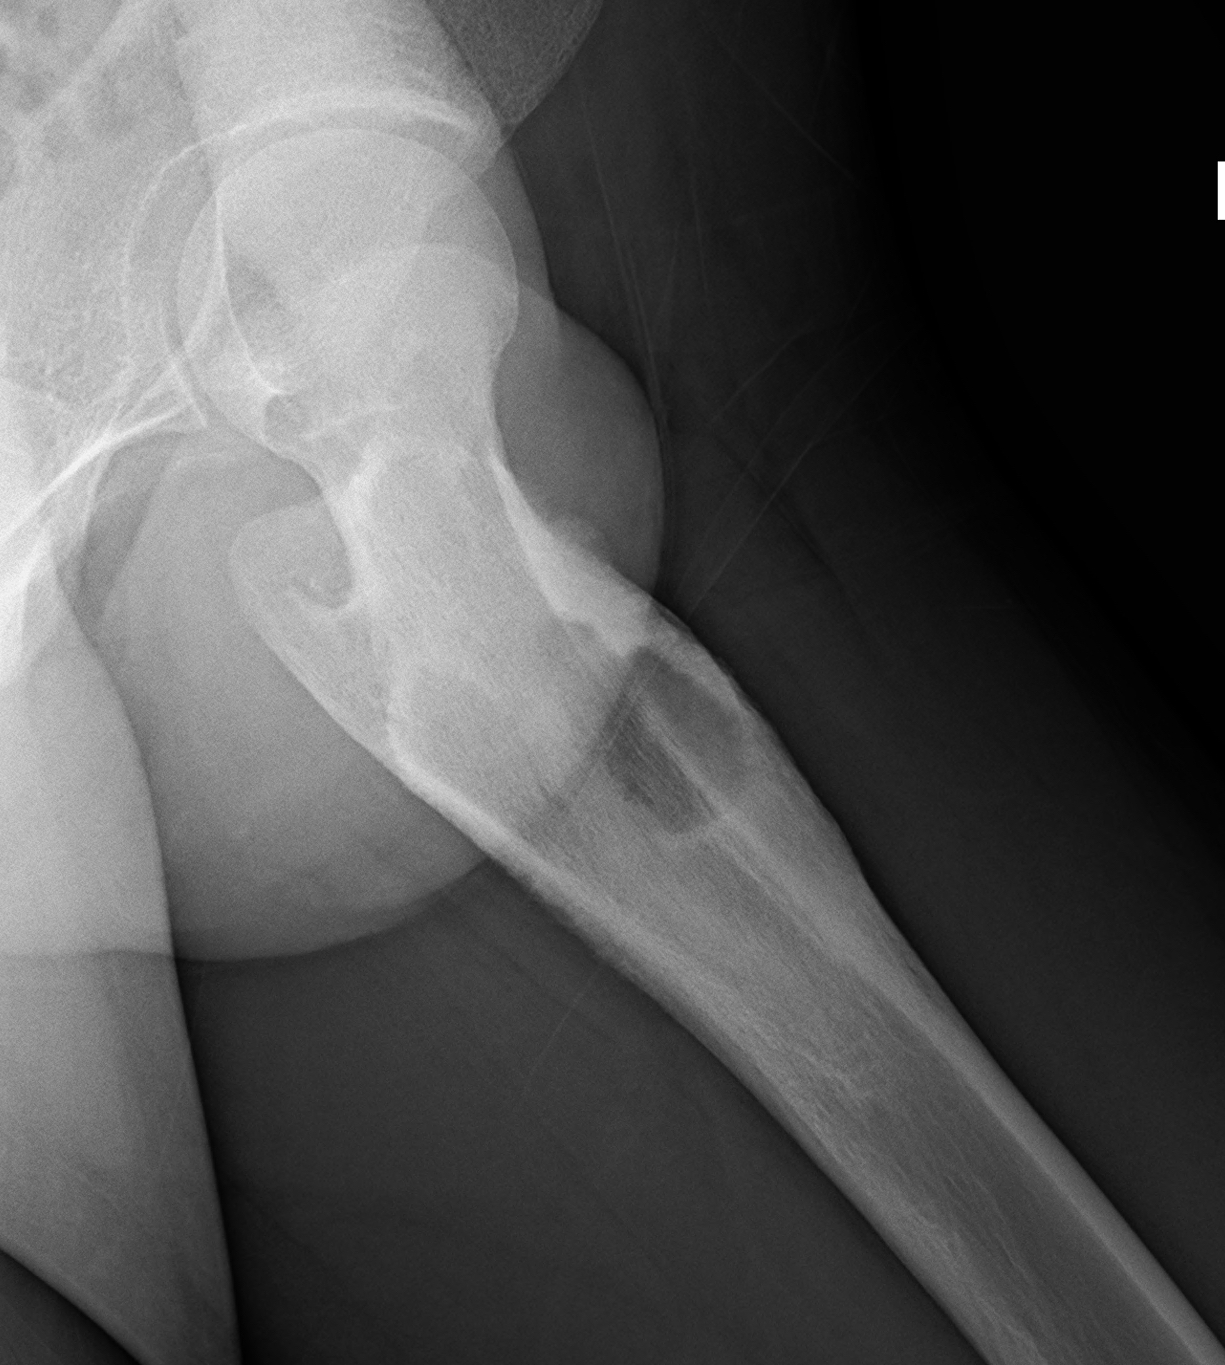

L'osteoblastoma è un tumore delle ossa che si localizza solitamente alla colonna vertebrale.

Il tumore è generalmente benigno, anche se esiste una forma più aggressiva.

La lesione interessa l'area corticale, piuttosto che la midollare, ed è prevalentemente sclerotica.